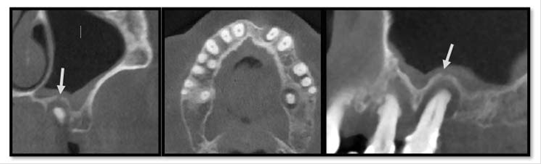

A 48-year-old white woman, described “pain in the left side of the face and in the left maxillary molars”, especially in the upper left first molar tooth. She was under treatment for type II diabetes mellitus and hypertension. The patient reported one month of nocturnal symptomatic episodes of pain and running nose. She also reported a cervical edema on the left side of the face and neck, exacerbated during movements of the head and neck. The medicine prescribed was continuous tramadol, but it wasn’t effective for pain control. An extraoral exam showed an inflammatory lymphadenopathy in the submandibular, ton-sillar, buccal and superficial left cervical lymph nodes chain on the left side. Pain was experienced during palpation without edema. The intraoral exam revealed a carious lesion in the left upper first molar with positive vertical percussion signs and pulp sensibility test compatible with irreversible pulpitis. The panoramic x-ray showed an extensive carious lesion in the upper left first molar with circumscribed bone rare-faction and defined limits, suggestive of a periapical cyst. The lesion involved the periapical region and alveolar extension of the maxillary sinus. For better evaluation of the relationship between the periapical lesion and the maxillary sinus, CBCT was done and showed a hypodense image in the periapical region of the left UFM with rupture of the cortical floor of the maxillary sinus, thick maxillary sinus mucosa, and expansion and rupture of the palatine cortical bone (figure 1). The diagnose was OMS associated with an infected radicular cyst the patient was referred for endodontic treatment.